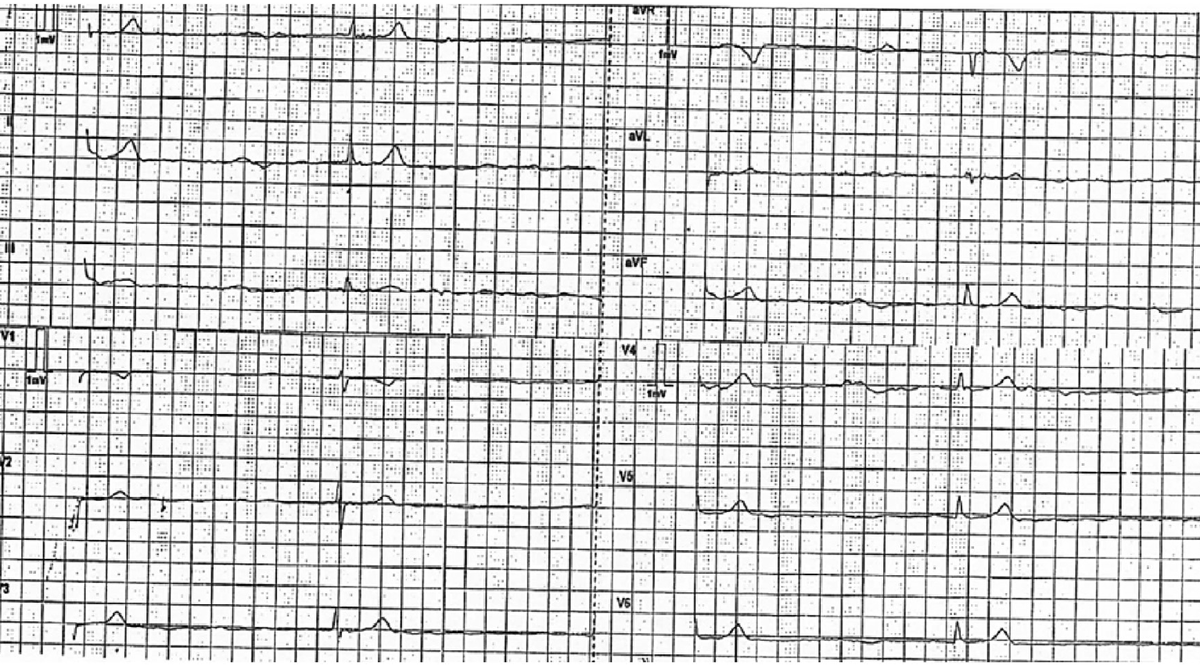

1時間ほど経過観察をしていたら、HR22の徐脈になってしまいました。